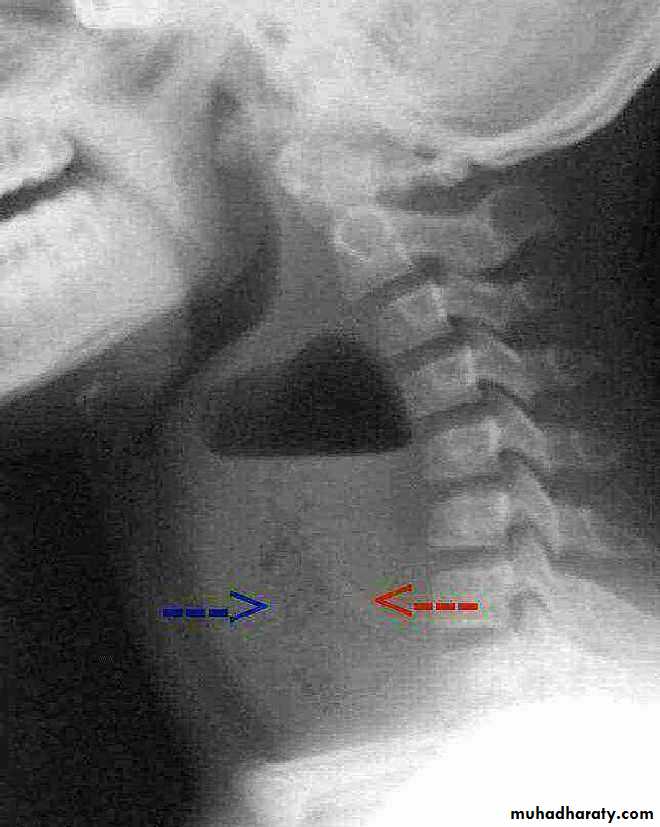

Orange arrow pharynx pushed anteriorly

Retrosternal Goiter

22.Retrophyrengeal abscess

25.retrosternal Goiter

26.retrosternal Goiter